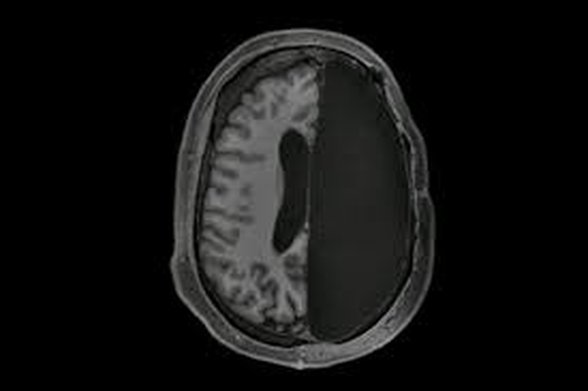

Beynin farklı bölgeleri spesifik faliyetler için özelleşmiştir. Örneğin konuşma ve el hareketleri için beynin Broca bölgesinin aktif olduğu, refleksin beyincik (pons), duygusal hafıza için hipotalamus gibi. O yüzden hangi fonksiyonun kaybolup hangi fonksiyonun korunduğu beynin neresinin zarar gördüğü veya kaybolduğu ile ilintili.